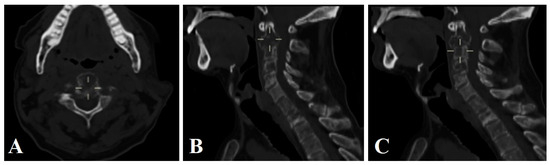

3.1.3. Clinical Case 3

3.3. Surgical Technique and Radiological Follow-Up